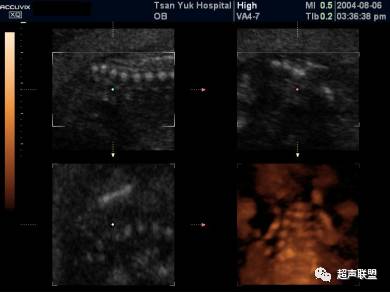

鼻骨

在脸的正中矢状面获取三维容积

最大模式进行三维重建成像

唐氏综合症胎儿单侧鼻骨缺失或发育不良

20 %左右的胎儿,1113, 鼻骨间有裂隙。